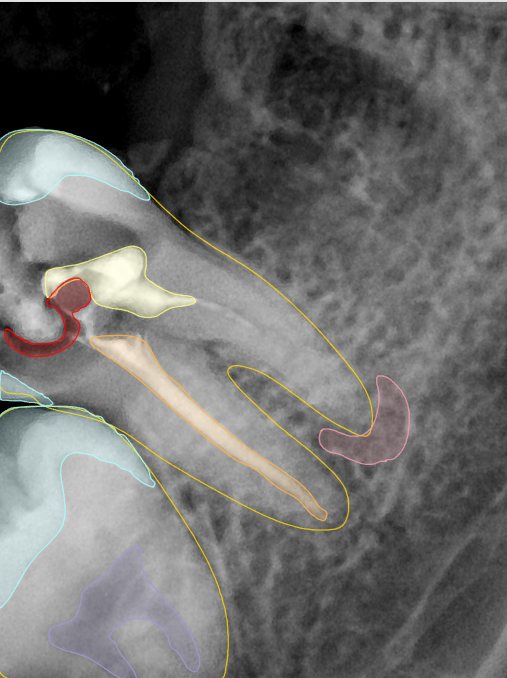

CR/DR 牙齿分割阶段记录

当前进展

- 完成了 CR/DR 牙齿相关分割训练

- 当前结果已经达到阶段预期,但仍有细节问题需要继续处理

相关测试

遇到的问题

- 训练过程中出现过 mask 下移问题

- 部分结果会出现 box 填充异常

- mask 边缘仍然有比较明显的锯齿感

参考

第二版算法问题测试

| 第一版 | 第二版 | 是否解决 | |

|---|---|---|---|

![]() | ![]() ![]() 边角识别有问题 龋齿识别不全 牙髓识别不全 | ![]() | 解决 |

![]() | ![]() 边角识别有问题 识别信息有误 自查(牙冠识别不全) | ![]() | 解决 |

![]() | ![]() ![]() 边角识别有误 大范围填充识别遗漏 | ![]() | 解决 |

![]() | ![]() 识别信息不全 | ![]() | 解决 |

![]() | ![]() ![]() 边角问题 牙胶识别不全 牙冠识别不全 | ![]() | 解决 |

![]() 换图片 | ![]() | ![]() 牙冠部分稍微白了一些就识别成小范围修补,部分判断异常 | 部分解决,修复类略敏感,牙冠部分稍微白了一些就识别成小范围修补,部分判断异常。 |

![]() | ![]() ![]() 牙冠识别不全 牙髓不全 根尖炎龋齿识别有误 | ![]() | 解决 |

![]() | ![]() | ![]() | 解决 |

![]() 换图片 | ![]() | ![]() | 解决 |

![]() | ![]() 牙冠识别有误 | ![]() | 解决 |

![]() 换图片 | ![]() ![]() 边角识别有误 | ![]() 修复类敏感 | 部分解决,图像过白,导致修复类判断异常。 |

![]() 换图片 | ![]() 牙冠识别不全 | ![]() 修复类敏感 | 部分解决,图像过白,导致修复类判断异常 |

结论:修复类出现了不鲁棒的情况,后续需要加入轮廓的扩充数据进行增强。